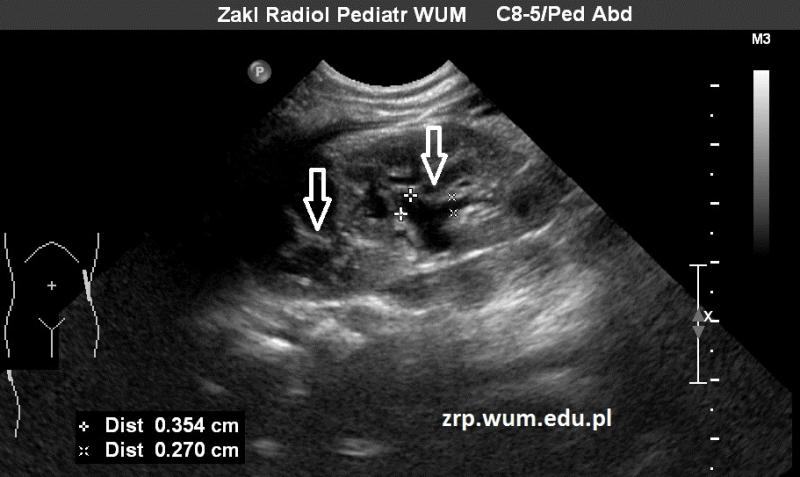

W badaniu usg stwierdzono cechy zdwojenia UKM nerki lewej (strzałki), z niewielkim poszerzeniem dolnego układu (pomiary).